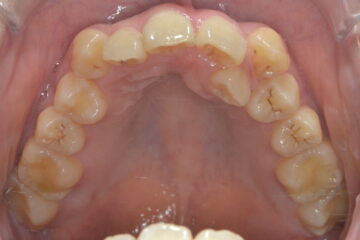

2025年10月(治療前)

2025年12月